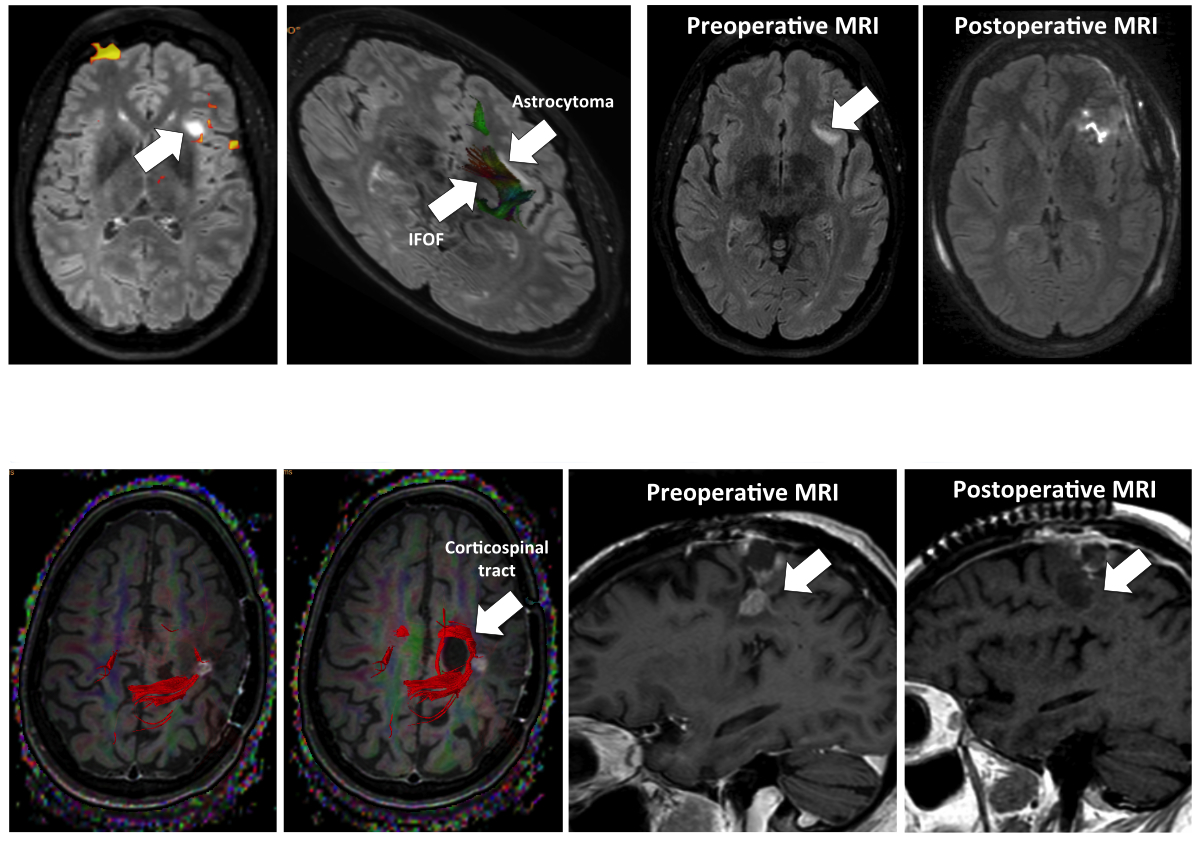

Figure 1 Illustrative cases benefiting from the combined use of awake surgery and intraoperative MRI. Case 1: Preoperative evolutive primary brain tumor (insular astrocytoma IDH 1 mutated) WHO II, in contact on its medium pole with the inferior fronto-occipital fasciculus (IFOF). Case 2: Recurrent (multioperated and irritiated) brain metastasis, localized in the central area, in contact with the corticospinal tract (in red, interrupted by the tumor).

Clinical assessment was performed by a board-certified neurosurgeon preoperatively and at 3, 6, and 12 months postoperatively using the Karnofsky performance score (KPS). The neuropsychological exam was performed by a specialized neuropsychologist (co-author OS) for patients' task-based functional MRI (fMRI) to check for their dominant hemisphere. Complementary diffusion tensor imaging by fibre tracking (DTI) was performed to evaluate the position of major fascicles including, but not limited to, the corticospinal tract, arcuate fasciculus, inferior fronto-occipital fasciculus (IFOF), and arcuate fasciculus (AF) [28]. Postoperative MRI was usually performed within the first 48 hours after surgery and at 3 and 6 months.